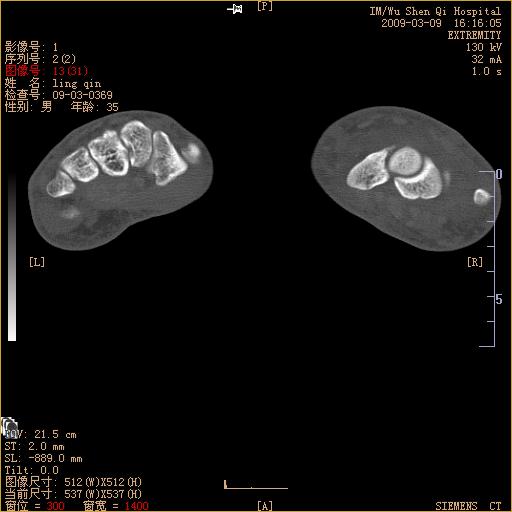

标题: CT18570:右手外伤10余天

请上传x线平片。舟状骨骨折可能大。

腕部有骨折、脱位,骨科面对ct片如何采取措施?三维一下。

请上传x线平片,腕骨多骨骨折

舟状骨骨折。

左侧舟骨及桡骨茎突骨折,第一掌骨基底部好像也有骨折,建议上传平片